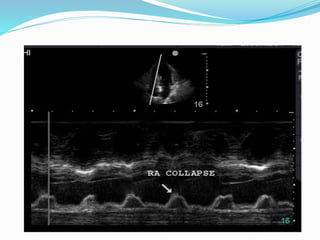

Cardiac tamponade- m

mode features

 Compressed RV (RVID<7mm)

 Increase in RV dimension with inspiration and

simultaneously decrease in LV dimension during

inspiration.

 Decrease mitral valve EF-slope with inspiration.

 Decrease mitral valve DE-amplitude with inspiration.

 RV diastolic collapse.(specific)

 RA diastolic collapse.(sensitive)

 Dilated IVC with blunted respiratory changes.

Cardiac tamponade- m modefeatures  Compressed RV (RVID<7mm)  Increase in RV dimension with inspiration and simultaneously decrease in LV dimension during inspiration.  Decrease mitral valve EF-slope with inspiration.  Decrease mitral valve DE-amplitude with inspiration.  RV diastolic collapse.(specific)  RA diastolic collapse.(sensitive)  Dilated IVC with blunted respiratory changes.